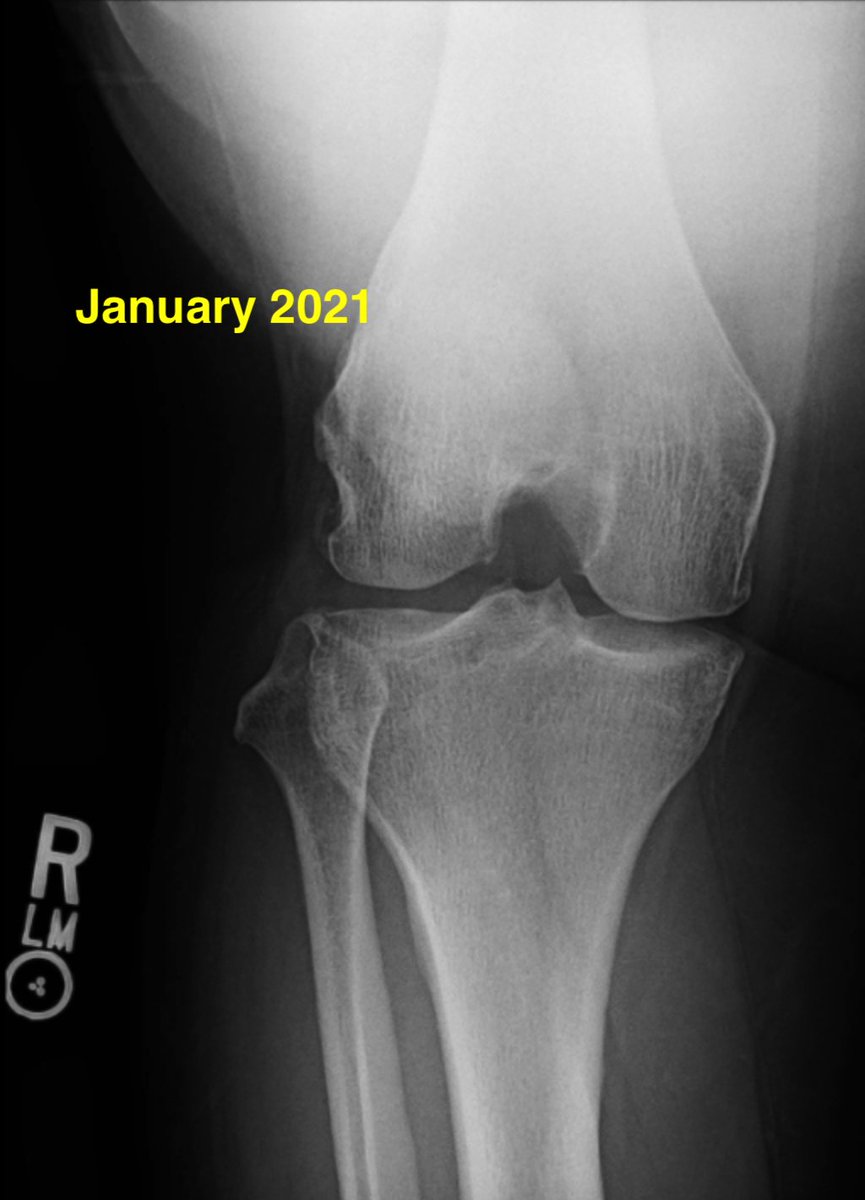

Meniscus root tears are important to recognize and address. Unfortunately, the natural history of a medial meniscus root tear can be seen in this patient when left untreated, with rapid progression of medial arthritis. #savethemeniscus #orthotwitter